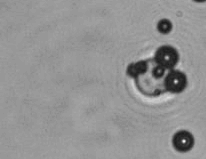

The dissolution of cell-bound lipid-shelled microbubbles occurs due to air compression at 2 atm, as depicted in a series of time-lapse images captured over 2 seconds.

AeroCytek creatively applies FDA-approved phospholipid-shelled microbubbles for reversible buoyancy-based cell sorting and as tunable artificial cells. These microbubbles have been employed to select, activate, and transduce T cells for ex vivo CAR-T cell production in a preclinical animal model. They can dissolve in solution instantly by increasing ambient pressure or spontaneously over a longer period. Functionally, these cell-like microbubbles (designated AeroCyte) can be categorized by their activities with cells into three groups: